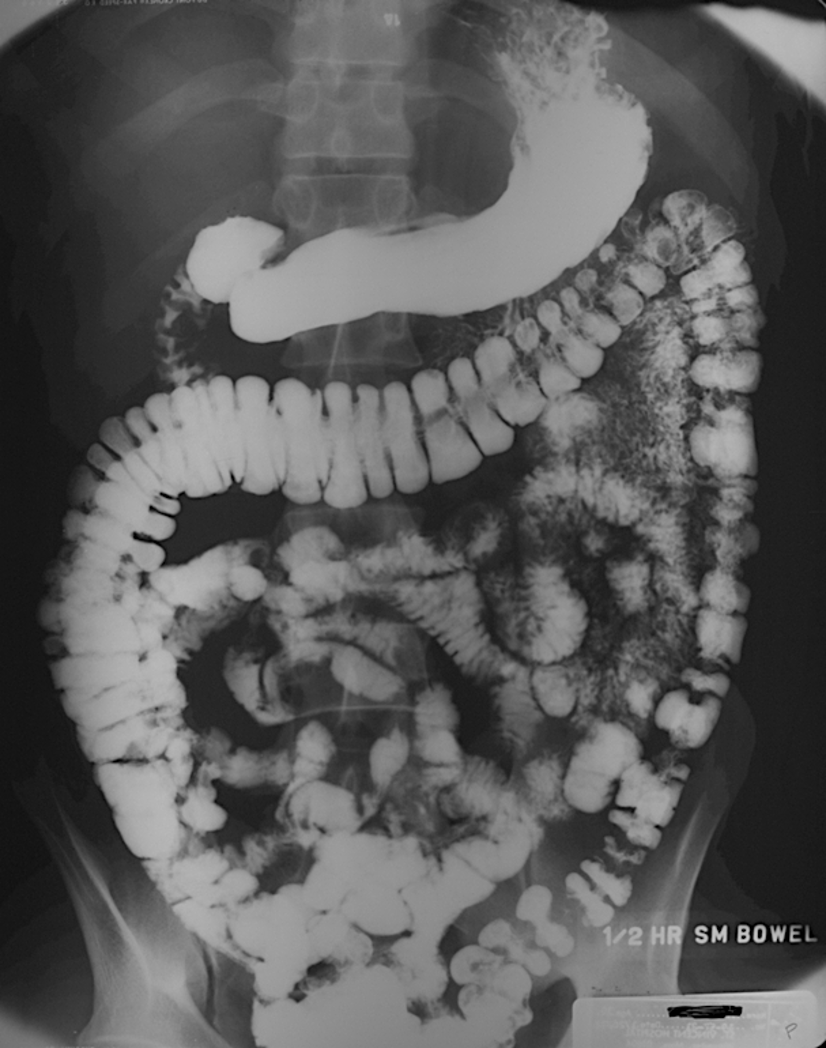

What is a barium enema study?

air and barium are both used as contrast agents

allows for excellent visualization of the mucosal surface of the colon

Explain how a barium swallow with follow through works

pt drinks barium contrast, and the barium goes though allow visiualiization of entire upper GI tract